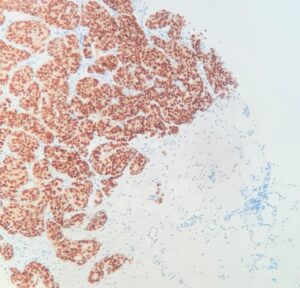

Receptor de Estrógenos

Una vez confirmado el diagnóstico se realizan pruebas adicionales para determinar el subtipo de cáncer. El análisis del receptor de estrógenos (RE) es crucial ya que un resultado positivo indica que el tumor es sensible a terapias hormonales.

Receptor de Estrógenos positivo. Núcleos marcados con DAB (marrón).